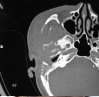

Segnaliamo su un uomo di 55 anni che ha presentato con scarico orecchio destro con diminuzione dell’udito per 5 mesi e proprio mal di orecchio per 2 mesi. Era sordo dolorante a inizio ripresa ma forte per 5 giorni accompagnati da esterno destro di gonfiore del viso [ Figura 1 ] ed è diminuito l’apertura della bocca per 5 giorni. No associata tinnito, vertigini, o altri sintomi costituzionali erano presenti. L’interessata canale uditivo esterno era gonfio e eritematosa. Il suo nervo facciale era intatto. Ad alta risoluzione di tomografia computerizzata (HRCT) di osso temporale mostrato irregolare dell’area osteolitica che coinvolge la porzione posteriore del giusto processo zigomatico e giunzione temporale zigomatico, cellula aria mastoide, cavità dell’orecchio medio con erosione di anteriore, laterale e superiore della parete. Vi è una evidenza di perifericamente potenziando la raccolta visto in tutto il processo zigomatico destro e misura 3,9 * 1,6 centimetri con gonfiore mal definita del tessuto molle di regione temporale destra (spazio masticatorio). Margine anteriore e posteriore di EAC mostra anche erosione [ figura 2 ]. Orecchio tampone inviare per la cultura e la sensibilità rinvasare venuto come pseudomonas aurigenosa. Abbiamo avviato antibiotici per via endovenosa, che ha portato in notevole miglioramento, la paziente ha subito un mastoidectomia radicale modificata con drenaggio di ascesso zigomatico. C’era un auto mastoidectomia e una massa granulare organizzata che riempe completamente la cavità mastoide con erosione completa del processo zigomatico e la presenza di un colesteatoma nell’attico. L’esame istopatologico del campione non mostra evidenza di malignità. I pazienti hanno esibito ottimo recupero post-operatorio, senza paralisi facciale, vertigini o altre complicazioni. La diagnosi di ascesso zigomatica associata a otite media non sicure è stato fatto.

Ad alta risoluzione di tomografia computerizzata di temporale osso irregolare dell’area osteolitica che coinvolge la porzione posteriore del giusto processo zigomatico e giunzione temporale zigomatico, cellula aria mastoide, cavità dell’orecchio medio con erosione di anteriore, laterale e